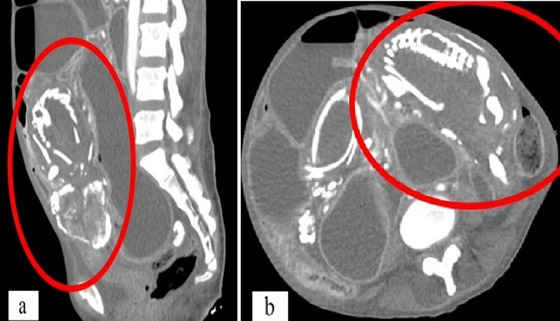

توفيت امرأة بسبب سوء التغذية الحاد بعد أن حملت جنيناً لم يولد بعد قرابة تسع سنوات داخل جسدها. وزارت المرأة، وهي في الأصل من الكونغو الأطباء في نيويورك وهي تشكو من تقلصات في المعدة وعسر الهضم وصوت غرغرة بعد تناول الطعام. وكشفت الفحوصات أن المرأة البالغة من العمر 50 عاماً لديها جنين متكلس ضغط على أمعائها، والذي يُعزى إلى إجهاض حدث قبل تسع سنوات.

الظاهرة النادرة، التي تم تسجيلها أقل من 300 مرة فقط، تحدث عندما يموت الجنين الذي ينمو خارج الرحم أثناء الحمل ولا يتم إطلاقه من الجسم. وهو من بين العديد من مضاعفات الحمل التي لها آثار طويلة الأمد على صحة الأم. ورفضت المريضة العلاج، قائلة إنها تعتقد أن حالتها الصحية مرتبطة بـ "تعويذة" ألقاها عليها شخص ما في إفريقيا. وتوفيت المرأة بعد 14 شهراً من وصولها إلى الولايات المتحدة. وقال الأطباء إنها ماتت من سوء التغذية الحاد أو الجوع.

وفي هذه الحالات، قد يكون سبب الوفاة في نهاية المطاف هو تدهور الأنسجة مما يؤدي إلى السكتة القلبية أو عدم انتظام ضربات القلب، وعدم انتظام ضربات القلب. وتشمل الأسباب الأخرى العدوى الناتجة عن ضعف جهاز المناعة. وبالنسبة لهذه المرأة، ظل "الطفل المتحجر" يضغط على الأمعاء. وتسبب هذا في انسداد أمعائها، مما يعني أن جسدها لم يعد قادراً على امتصاص العناصر الغذائية الحيوية. وقال الدكتور وسيم سوس، خبير الطب الباطني في جامعة ولاية نيويورك الطبية التي أبلغت عن الحالة، إن المريضة "رفضت التدخل خوفاً من الجراحة، ولسوء الحظ، توفيت بسبب سوء التغذية الحاد في سياق انسداد الأمعاء المتكرر والخوف المستمر من طلب الرعاية الطبية".

ولم يستطع الأطباء تحديد مكان حدوث الحمل في الجسم، لكنهم خلصوا إلى أنه من المحتمل أن يكون خارج الرحم. وعندما يموت الطفل، يكون حجمه أكبر من أن يمتصه الجسم مرة أخرى. ونتيجة لذلك، يقرر الجهاز المناعي أن الجنين الميت يشكل تهديداً للجسم. ويؤدي هذا إلى ترسب رواسب غنية بالكالسيوم على الجنين، وتغليفه تدريجياً بقشرة متكلسة أو تحويله إلى حجر. وتوقف الجنين - الذي كان من الممكن أن يكون الطفل التاسع للمرأة - عن النمو بداخلها في الأسبوع 28. لكن بدلاً من الإجهاض، عانت من الحالة المعروفة باسم lithopedion. وتحدث الحالة عندما يتكون الحمل في البطن بدلاً من الرحم. وفي هذه الحالة لا تصل كمية كافية من الدم إلى الطفل، مما يؤدي إلى فشل الحمل. ولا يستطيع الجسم طرد الجنين أيضاً، مما يؤدي إلى مضاعفات مميتة.